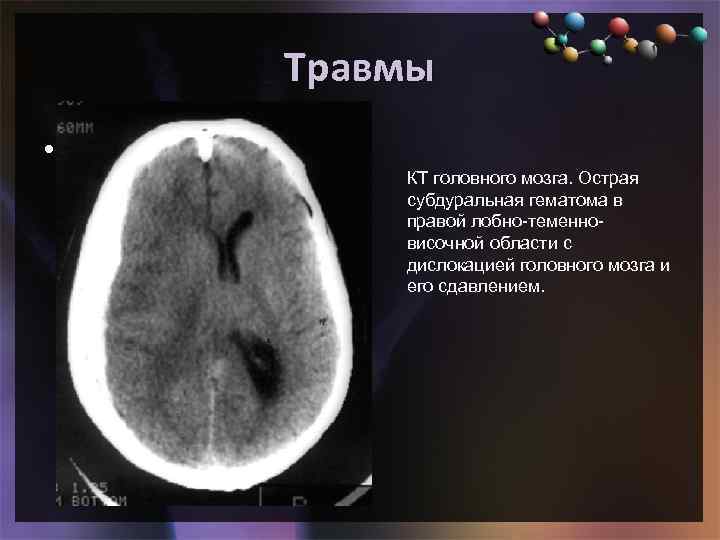

Травмы • Подзаголовок слайда КТ головного мозга. Острая субдуральная гематома в правой лобно-теменновисочной области с дислокацией головного мозга и его сдавлением.

Травмы • Подзаголовок слайда КТ головного мозга. Острая субдуральная гематома в правой лобно-теменновисочной области с дислокацией головного мозга и его сдавлением.